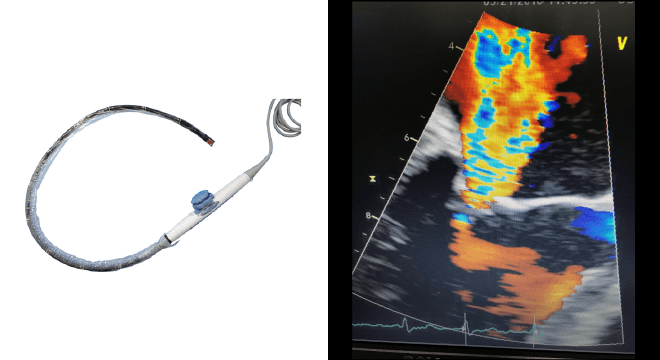

カテーテル治療であるマイトラクリップは、鼠径部(股の付け根)の静脈から挿入し、右心房から左心房を経て、僧帽弁の逆流部分にクリップを行う治療です。

胸に傷口は残らないため、手術からの回復も早く、身体への負担が少ないのが特徴です。手術のメリットが大きい方にはまず、外科的手術(弁形成術、置換術)をお勧めしています。しかし患者さんの年齢、併存症や心臓の機能が極端に悪いため、これまで手術を受けるのが難しかった患者さんの中でも、経食道エコー図(後述)での解剖的適合を満たす場合に、当院ではマイトラクリップをお勧めしています。

| 経食道心エコー図検査 (経食道心臓超音波検査) |

横を向いた状態で、胃カメラのように直径1cm程度の超音波プローベを食道の中に入れ、心臓を裏側から超音波で検査します。経胸壁心臓超音波検査に比べ、肺や肋骨が邪魔にならないため、より鮮明に心臓の弁や逆流の観察が可能です。特にマイトラクリップは、弁の合わさりや長さ、幅に制約(解剖学的適合)がありますので、お受けいただくすべての患者さんは、術前にこの検査を受けて頂く必要があります。 |

僧帽弁狭窄症

マイトラクリップにより弁尖(前尖、後尖)同士を把持しますので、逆に弁が開きにくくなり、僧帽弁狭窄症が生じることがあります。術中に経食道心エコー図で観察し、狭窄がどこまで許容できるか、僧帽弁の逆流の制御を加味して、判断いたします。